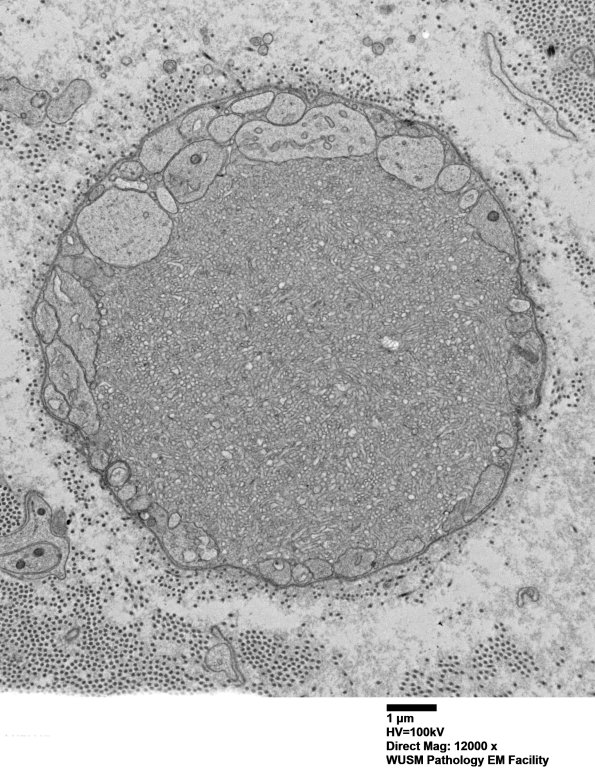

An axonal spheroid accompanied by Schwann cell processes. (electron micrograph)